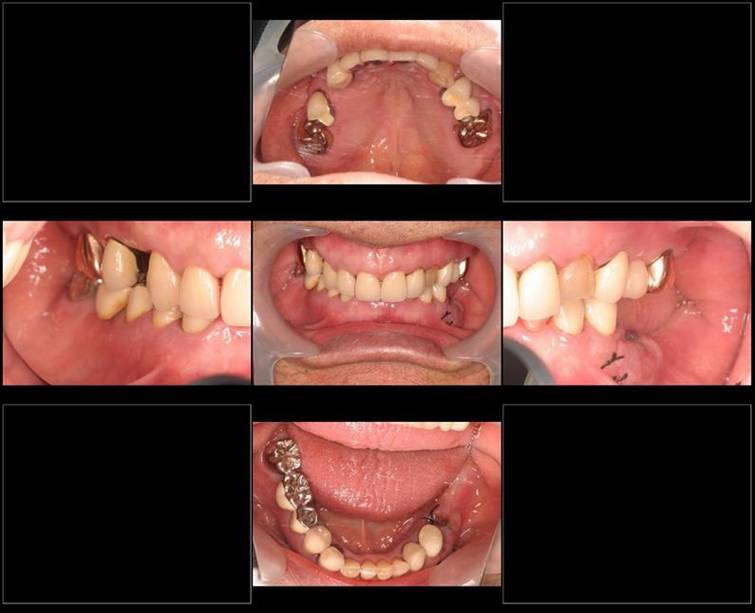

歯周病で抜歯せざるを得ず、インプラントを希望されたケース(使用インプラントはスプライン)

術前。すべての歯が歯周病の末期状態でブリッジ全体がうごいて噛めないとの訴え。右上の犬歯が腫れていました

固定式のブリッジが入っていましたが歯周病で動いています

下顎前歯部には歯石の沈着がみられます